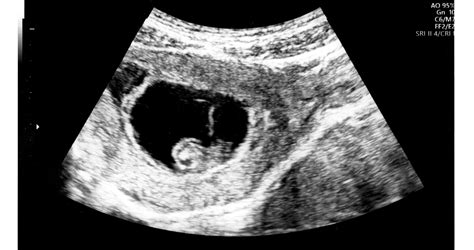

A várandósság 29. hetében a kismama már a nyolcadik hónapban jár, ami a harmadik, utolsó és leghosszabb trimeszterbe esik. Ez az időszak ugrásszerű fejlődést hoz mind a magzat, mind az édesanya számára, és a felkészülés jegyében telik.

A 29. hétre a magzat már rendkívül hasonlít egy újszülötthöz. Testarányai és vonásai jelentősen fejlődtek az elmúlt hetekben, és a szülésig már nem következnek be drasztikus változások. A súlygyarapodás kiemelten fontos ebben az időszakban, mivel a magzat zsírszövetből képez tartalékokat. Erre azért van szüksége, mert születése után az édesanya szervezetében kezdetben még nem termelődik teljes értékű anyatej. Az újszülött kezdetben kissé veszít súlyából, majd a harmadik napon kezdi újra hízni, amikor már az anyatej révén értékes kalóriákhoz és zsírral jut a szervezetébe.

A 29. héten a kismama pocakja a magzat növekedésével arányosan gyarapszik. A magzat folyamatosan mozog, és ezek a mozgások egyre erőteljesebben érzékelhetőek, ahogy a magzat növekszik és egyre kisebb a hely az anyaméhben. Amíg van elegendő hely, a magzat aktívan mozog.